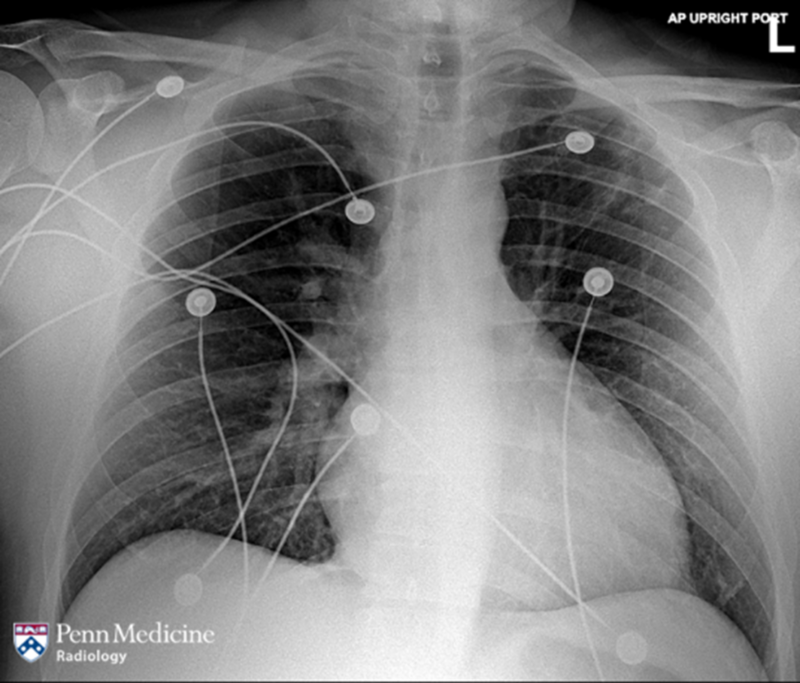

59-year-old man with hypoxic respiratory failure

A 59-year-old man with a past medical history of progressive fibrotic lung disease developed hypoxic respiratory failure secondary to an interstitial lung disease flare requiring extracorporeal membrane oxygenation (ECMO) and eventual bilateral orthotopic lung transplantation (BOLT).